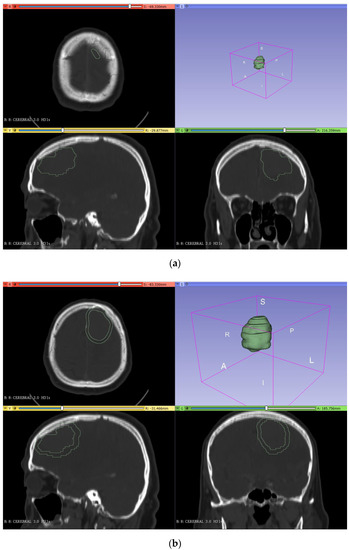

2.2.3. Brain Mold

In the making of the mold of the brain, the first step was to join the segmented model of the skull and the tumor (in the segment editor, ‘logical operators’ tool, ‘add’ operation) so that this mold had the shape of the tumor inside (Figure 4a). Then, the thickness was increased by 3 mm (‘margin’ tool) so that the molded brain had 3 mm of clearance with the skull. Finally, the model was cut (‘scissors’ tool) following the same plane as in the skull cutting (Figure 4b).

Figure 4.

Segmentation (a) and creation of the brain mold (b) from the DICOM images in 3DSlicer.